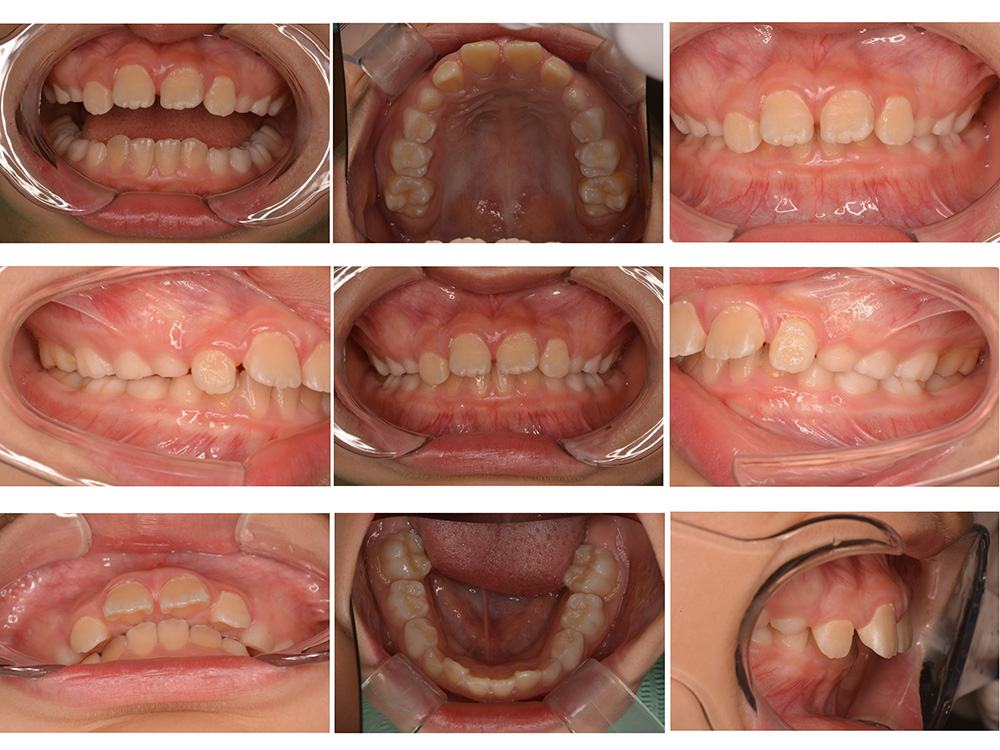

世代・性別

10歳女性

主訴

前歯が出ているのを治したい

治療内容

筋機能矯正治療(治療途中)

治療期間

4ヶ月

治療費

27万円(税別)

治療のリスク

歯の移動に伴う痛み